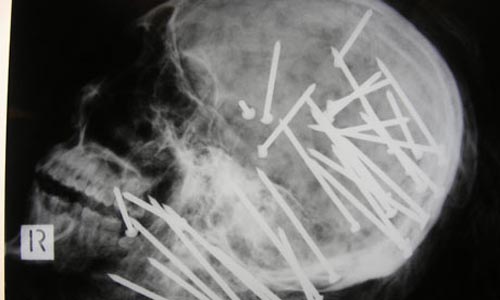

Hàng tá chiếc đinh găm vào đầu bệnh nhân, búp bê Barbie mắc trong vùng kín, kim tiêm gãy trong đùi, nhẫn đính hôn trong bụng... là những ca mắc dị vật lạ đời nhất.

Đinh găm chi chít trong đầu người từ một cây súng bắn đinh